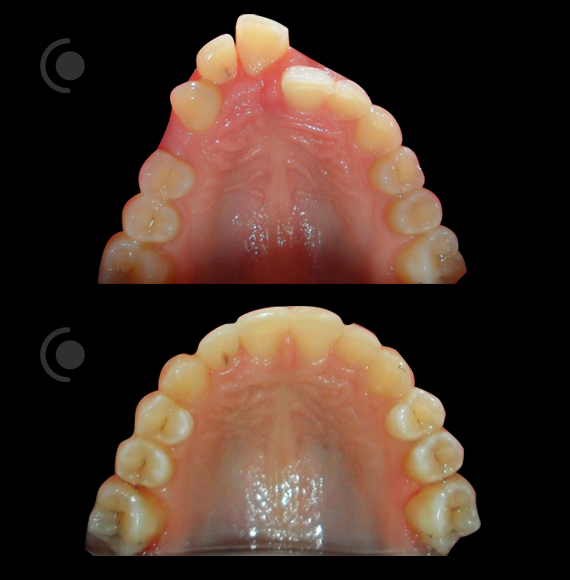

O našoj kvaliteti najbolje govore naši rezultati!

Centar za ortodonciju Petra Džapo